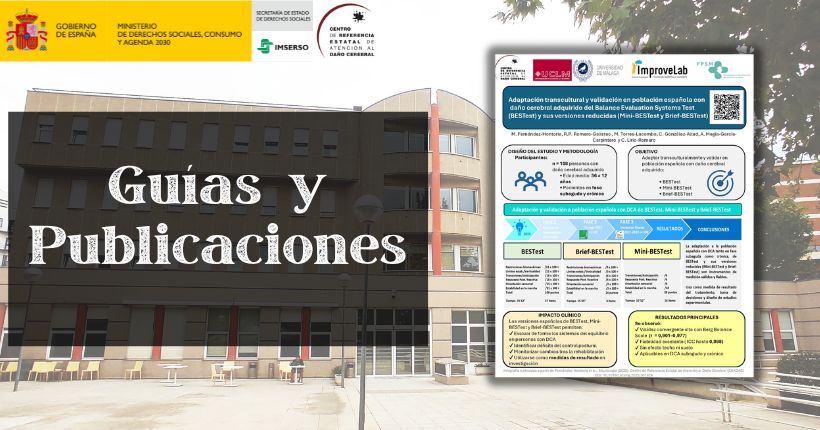

Infografía: Adaptación transcultural y validación a la población española con daño cerebral adquirido de la Prueba de Sistemas de Evaluación del Equilibrio (BESTest) y sus versiones reducidas (Mini-BESTest y Brief-BESTest)

Hoy compartimos la infografía del artículo Adaptación transcultural y validación a la población española con daño cerebral adquirido de la Prueba de Sistemas de Evaluación del Equilibrio (BESTest) y sus versiones reducidas (Mini-BESTest y Brief-BESTest), publicado recientemente en la revista Neurología y en el que ha participado Marta Fernández Hontoria, fisioterapeuta del Ceadac, Las alteraciones del equilibrio son una de las consecuencias más frecuentes tras un daño cerebral adquirido (DCA) y pueden afectar de forma significativa a la movilidad, la autonomía personal y la participación en las actividades de la vida diaria. Por este motivo, la evaluación del equilibrio constituye un aspecto fundamental en los procesos de valoración y seguimiento dentro de la neurorrehabilitación. El objetivo del estudio fue adaptar transculturalmente al español y analizar las propiedades psicométricas del BESTest y de sus versiones reducidas en personas con daño cerebral adquirido. El estudio se desarrolló en varias fases. En primer lugar, se llevó a cabo el proceso de adaptación transcultural del instrumento. Posteriormente se realizó un estudio piloto y, finalmente, se evaluaron las propiedades psicométricas de las versiones finales en una muestra de 108 personas con daño cerebral adquirido. El BESTest es una herramienta de evaluación del equilibrio basada en sistemas que permite analizar distintos componentes del control postural. Sus versiones reducidas, Mini-BESTest y Brief-BESTest, ofrecen alternativas más breves que facilitan su aplicación en la práctica clínica. Los resultados del estudio muestran que las versiones españolas del BESTest, Mini-BESTest y Brief-BESTest presentan alta validez y fiabilidad para la evaluación del equilibrio en personas con daño cerebral adquirido, tanto en fase subaguda como crónica. La disponibilidad de estas herramientas adaptadas y validadas en población española contribuye a mejorar la evaluación clínica del equilibrio y facilita su uso como medida de resultado en rehabilitación, apoya a la toma de decisiones clínicas y favorece el desarrollo de nuevas investigaciones en neurorrehabilitación. Entradas relacionadas Adaptación transcultural y validación a la población española con daño cerebral adquirido de la Prueba de Sistemas de Evaluación del Equilibrio (BESTest) y sus versiones reducidas (Mini-BESTest y Brief-BESTest)

Adaptación transcultural y validación a la población española con daño cerebral adquirido de la Prueba de Sistemas de Evaluación del Equilibrio (BESTest) y sus versiones reducidas (Mini-BESTest y Brief-BESTest)

Hoy en el blog compartimos el estudio Adaptación transcultural y validación a la población española con daño cerebral adquirido de la Prueba de Sistemas de Evaluación del Equilibrio (BESTest) y sus versiones reducidas (Mini-BESTest y Brief-BESTest) publicado en la revista Neurología. En este estudio ha participado Marta Fernández Hontoria, fisioterapeuta del Ceadac. Además, el centro ha colaborado tanto en el reclutamiento de la muestra como en la cesión de sus instalaciones para llevar a cabo las evaluaciones. Introducción Las medidas de evaluación de equilibrio suelen estar validadas en población general o en personas mayores, y escasas veces en población con afectación neurológica. El objetivo de este estudio es la adaptación transcultural y validación de la prueba de sistemas de equilibrio (BESTest) y sus versiones reducidas Mini-BESTest y Brief-BESTest en población española con daño cerebral adquirido. Métodos El estudio se dividió en tres fases: Traducción y adaptación de las pruebas. Prueba piloto de la versión adaptada. Evaluación de propiedades psicométricas (fiabilidad y validez). Se utilizó como variable criterio la escala de equilibrio de Berg; la validez de constructo se evaluó mediante el análisis factorial exploratorio de todos los ítems de cada prueba, y la fiabilidad se comprobó mediante alfa de Cronbach e intervalo de correlación intraclase. Resultados Participaron 108 personas en fase subaguda y crónica tras sufrir daño cerebral. El análisis psicométrico de las tres pruebas mostró buena validez convergente, consistencia interna, acuerdo inter-evaluador (0,998-0,969) y reproductibilidad (0,985-0,989). Se detectó validez convergente con la escala de equilibrio de Berg (r=0,901, p<0,001; r=0,977, p <0,001; r= 0,852, p <0,001, respectivamente) y otras escalas de marcha y equilibrio. No se ha encontrado efecto techo ni suelo en las adaptaciones a población española con daño cerebral adquirido de BESTest, Mini-BESTest y Brief-BESTest. Conclusiones Las tres pruebas son válidas y fiables, siendo BESTest la mejor opción para evaluar el equilibrio en personas con daño cerebral adquirido, tanto en fase subaguda como crónica, puesto que incluye dominios que otras herramientas no evalúan. Fuente Fernández-Hontoria, M., Romero-Galisteo, R.P.,Torres-Lacomba, M., et al. (2025). Adaptación transcultural y validación a la población española con daño cerebral adquirido de la Prueba de Sistemas de Evaluación del Equilibrio (BESTest) y sus versiones reducidas (Mini-BESTest y Brief-BESTest). Revista Neurología Vol 40, nº 8. DOI: 10.1016/j.nrl.2025.501929 Puede leer el artículo completo en el siguiente enlace.